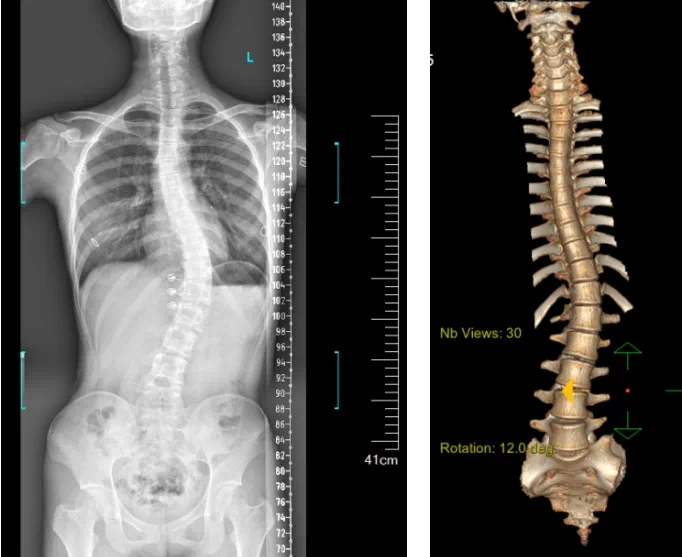

患者為一名16歲女孩,發(fā)現(xiàn)脊柱側(cè)彎1年,到南方醫(yī)院贛州醫(yī)院脊柱外科求診。經(jīng)查體,患者左右胸廓不對(duì)稱,雙肩等高,左肩胛骨隆起,背側(cè)呈“剃刀背”畸形,胸腰段棘突偏離正中線,胸腰段脊柱左側(cè)凸畸形;各棘突無(wú)壓痛及叩擊痛,右側(cè)腰部凹陷,胸腹及腰背部感覺(jué)正常。檢查發(fā)現(xiàn)患者特發(fā)性脊柱側(cè)彎,Lenke5C型,主胸彎51°。患者及家屬對(duì)外觀不滿意,為改善外觀及功能,要求手術(shù)矯形治療。

據(jù)悉脊柱側(cè)彎手術(shù)治療后可以保持軀干平衡,改善外觀并防止畸形進(jìn)一步發(fā)展。患者的生活質(zhì)量得到提高,進(jìn)而減少脊柱過(guò)度畸形可能帶來(lái)的疾病的發(fā)生率,外觀上的積極變化往往也能帶來(lái)患者心理與精神的積極變化。臨床上會(huì)綜合考慮患者的年齡、側(cè)彎程度、進(jìn)展趨勢(shì)、骨質(zhì)條件、鄰近節(jié)段情況、手術(shù)節(jié)段等因素,合理采用個(gè)性化的手術(shù)方式進(jìn)行治療。然而,由于脊柱神經(jīng)血管密布,手術(shù)操作相對(duì)復(fù)雜,手術(shù)難度高、風(fēng)險(xiǎn)大,傳統(tǒng)脊柱側(cè)彎的手術(shù)方式往往有較高的神經(jīng)或脊髓損傷風(fēng)險(xiǎn)。故此次科室決定開(kāi)展機(jī)器人輔助導(dǎo)航下脊柱側(cè)彎矯形、植骨融合內(nèi)固定手術(shù)。術(shù)前,醫(yī)生團(tuán)隊(duì)在機(jī)器人多維度圖像融合智能手術(shù)規(guī)劃功能的輔助下,預(yù)先規(guī)劃了理想的置釘路徑。術(shù)中,天璣骨科手術(shù)機(jī)器人準(zhǔn)確遵循術(shù)前規(guī)劃,根據(jù)配準(zhǔn)結(jié)果,實(shí)時(shí)定位并準(zhǔn)確執(zhí)行置釘操作,所有導(dǎo)針均用電鉆置入,一次性成功,協(xié)助醫(yī)生順利完成手術(shù)。最終,在麻醉科、手術(shù)室密切配合下,歷時(shí)3小時(shí)成功完成側(cè)彎矯形術(shù),出血量?jī)H500ml。術(shù)后,患者恢復(fù)良好,大小便及下肢神經(jīng)運(yùn)動(dòng)感覺(jué)正常。

圖為置釘后